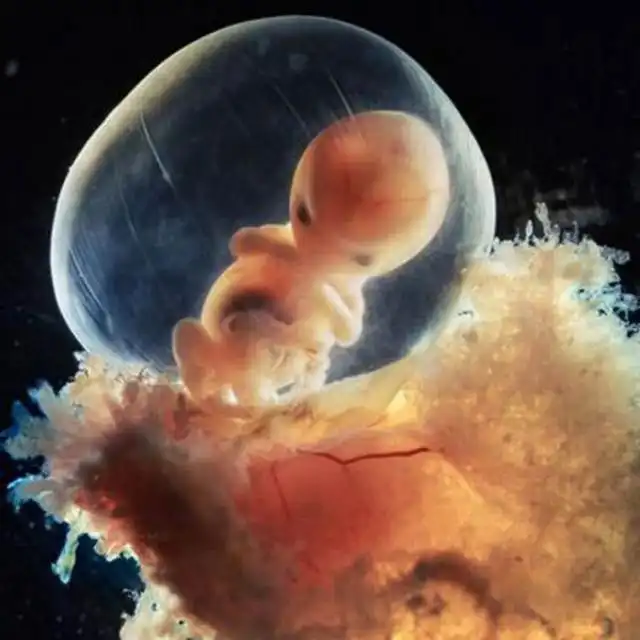

Через неделю зародыш, скользя вниз по фаллопиевой трубе, переселяется в матку...

Эмбрион, прикрепленный к слизистой матки (+8 дней)

Развитие эмбриона. Серым цветом - будущий головной мозг. (+22 дня)

24 дня. Скелета у месячного зародыша еще нет - есть только сердце, оно начинает пульсировать на 18-й день